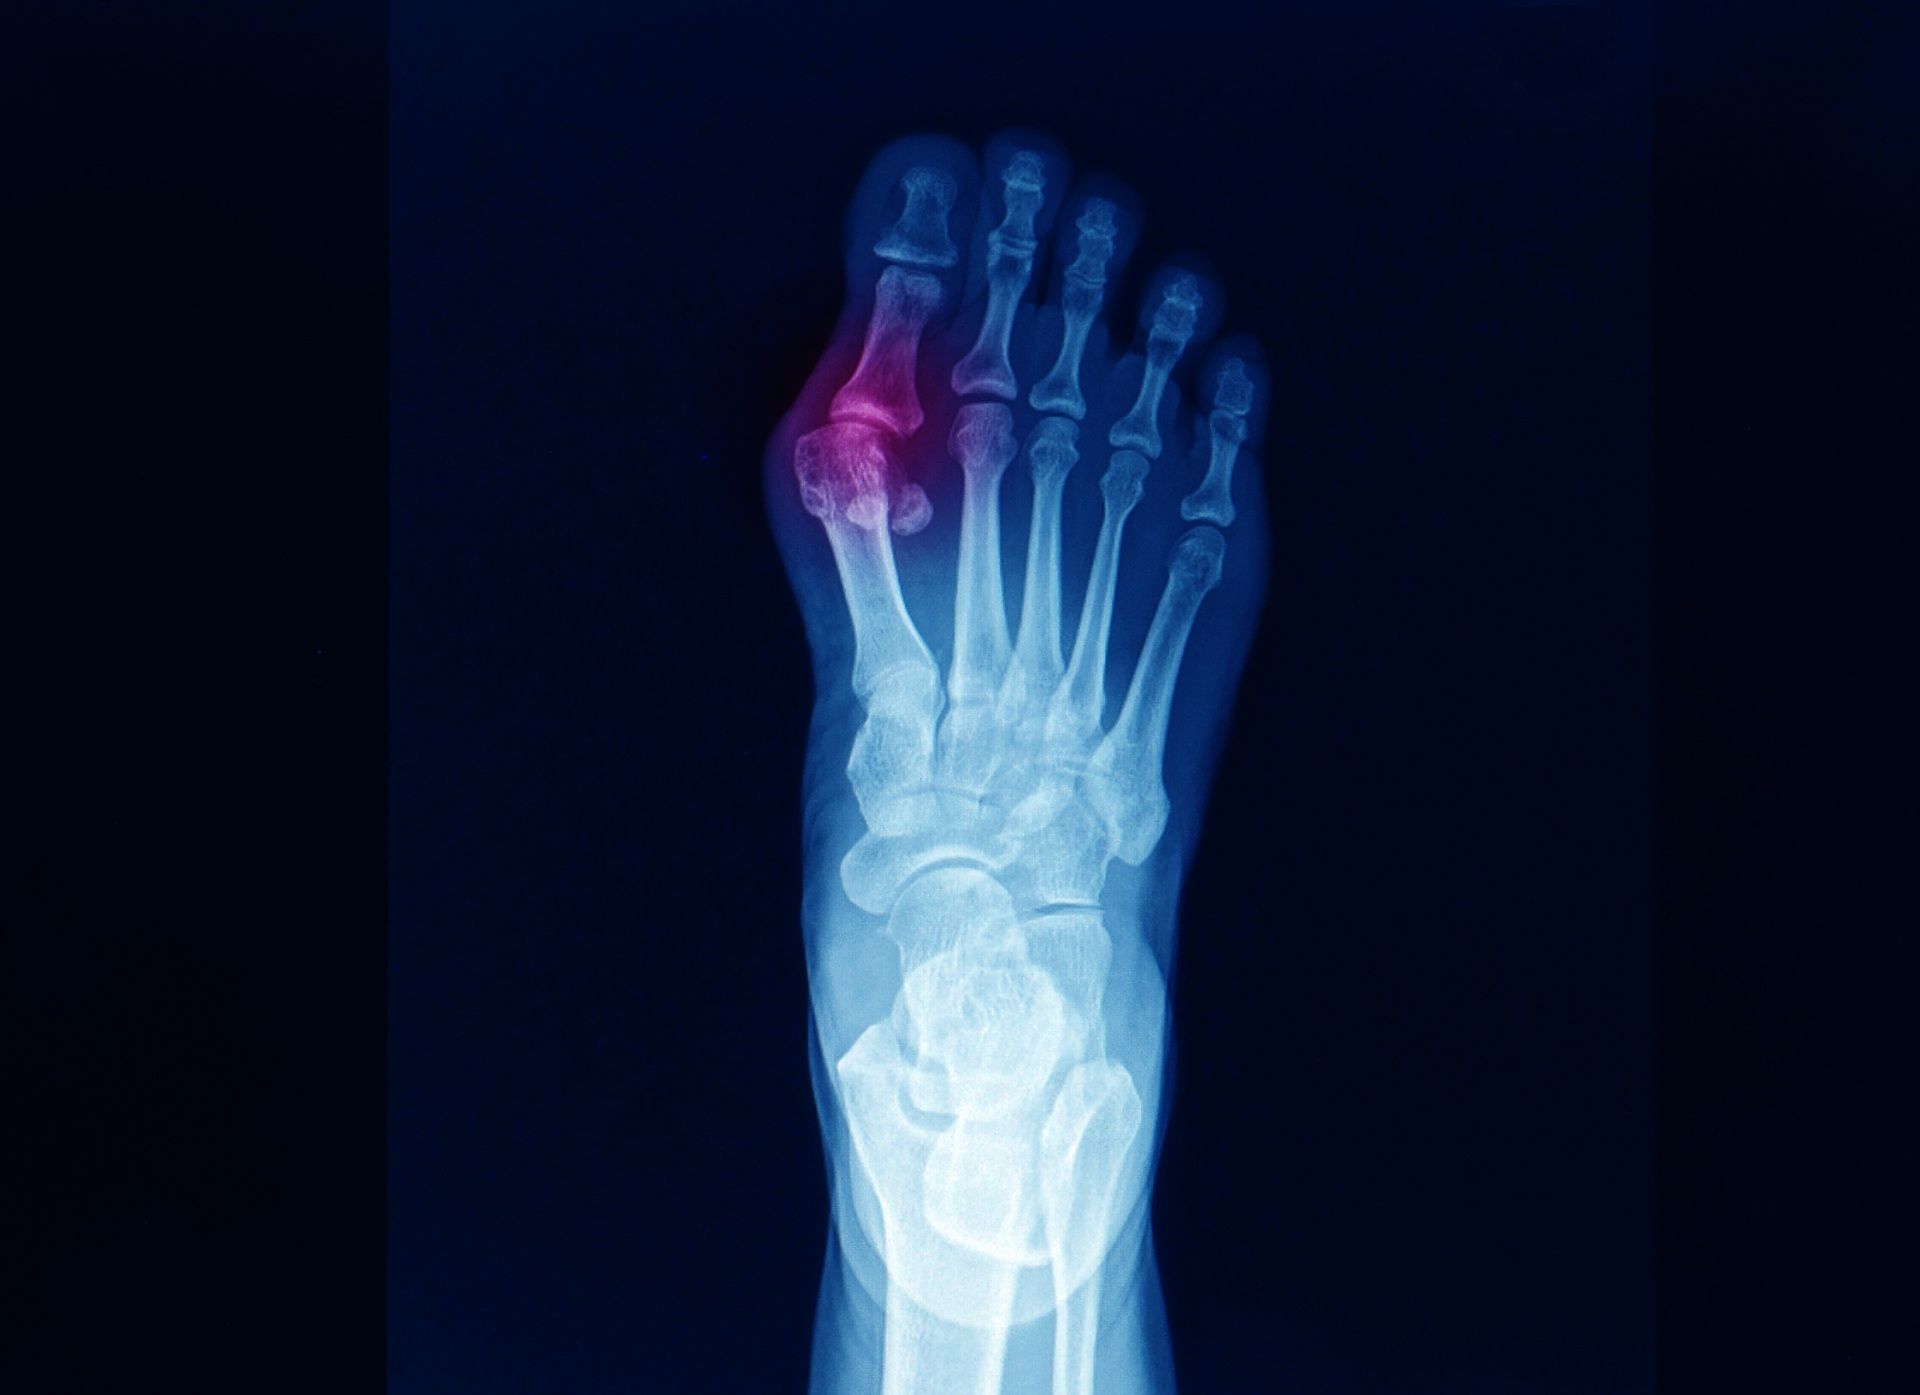

At Family Foot and Ankle Centers, our podiatric medicine practice specializes in diagnosing and treating comprehensive disorders of the foot, ankle, and related leg structures. Our experienced physicians utilize evidence-based, hands-on approaches that begin with thorough patient examinations and attentive listening to ensure accurate diagnoses and effective treatment plans. We possess advanced diagnostic capabilities and can perform both minimally invasive and reconstructive surgical procedures when necessary, prescribe appropriate medications, and recommend therapeutic exercises tailored to your needs.